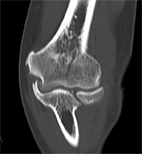

相對於退化性膝關節炎,肘關節炎並不常見,雖然說肘關節炎盛行率不高,但罹患此疾病,仍是會影響病患的生活品質。其中又以肘關節骨折或韌帶損傷使得關節面不平整,進而導致軟骨磨損,是最常見造成肘關節炎的因素。一般在治療上,會考量病患是否因肘關節長骨刺(如:圖一)或是碎骨使得在伸直或彎曲時產生疼痛,則此類病患可以考慮使用關節鏡手術清除碎骨、骨刺,但若有嚴重的關節變形則會採用一般開放性手術治療。有了這些技術,就可以不用換人工肘關節。

圖一、退化性肘關節電腦斷層影像